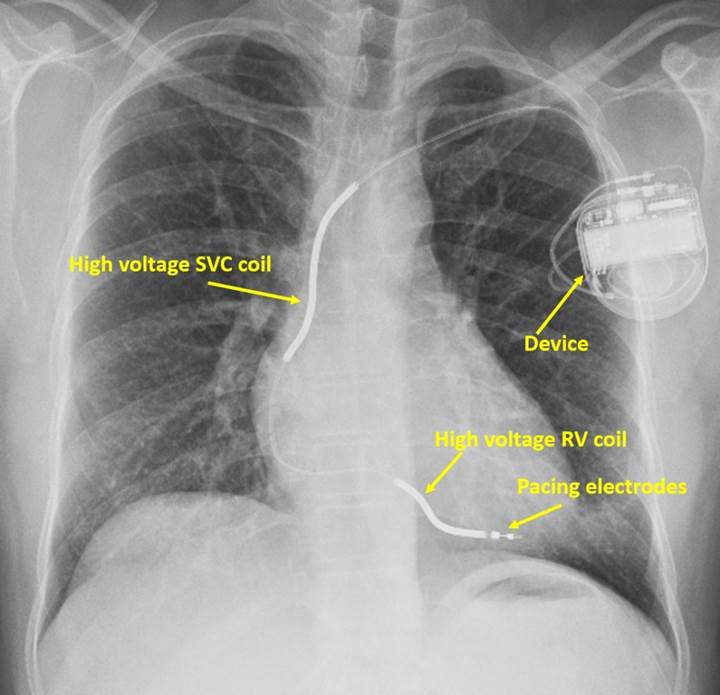

Implantable Cardioverter-Defibrillator (ICD)

An ICD is a small, battery-powered device surgically implanted in the chest of patients at high risk for life-threatening arrhythmias. It continuously monitors the heart’;s rhythm. If it detects VF or VT, it automatically delivers a low- or high-energy shock directly to the heart muscle via wires (leads). It acts as a 24/7 guardian against sudden cardiac death.

An ICD is implanted under the skin to provide constant monitoring and immediate treatment for dangerous arrhythmias.